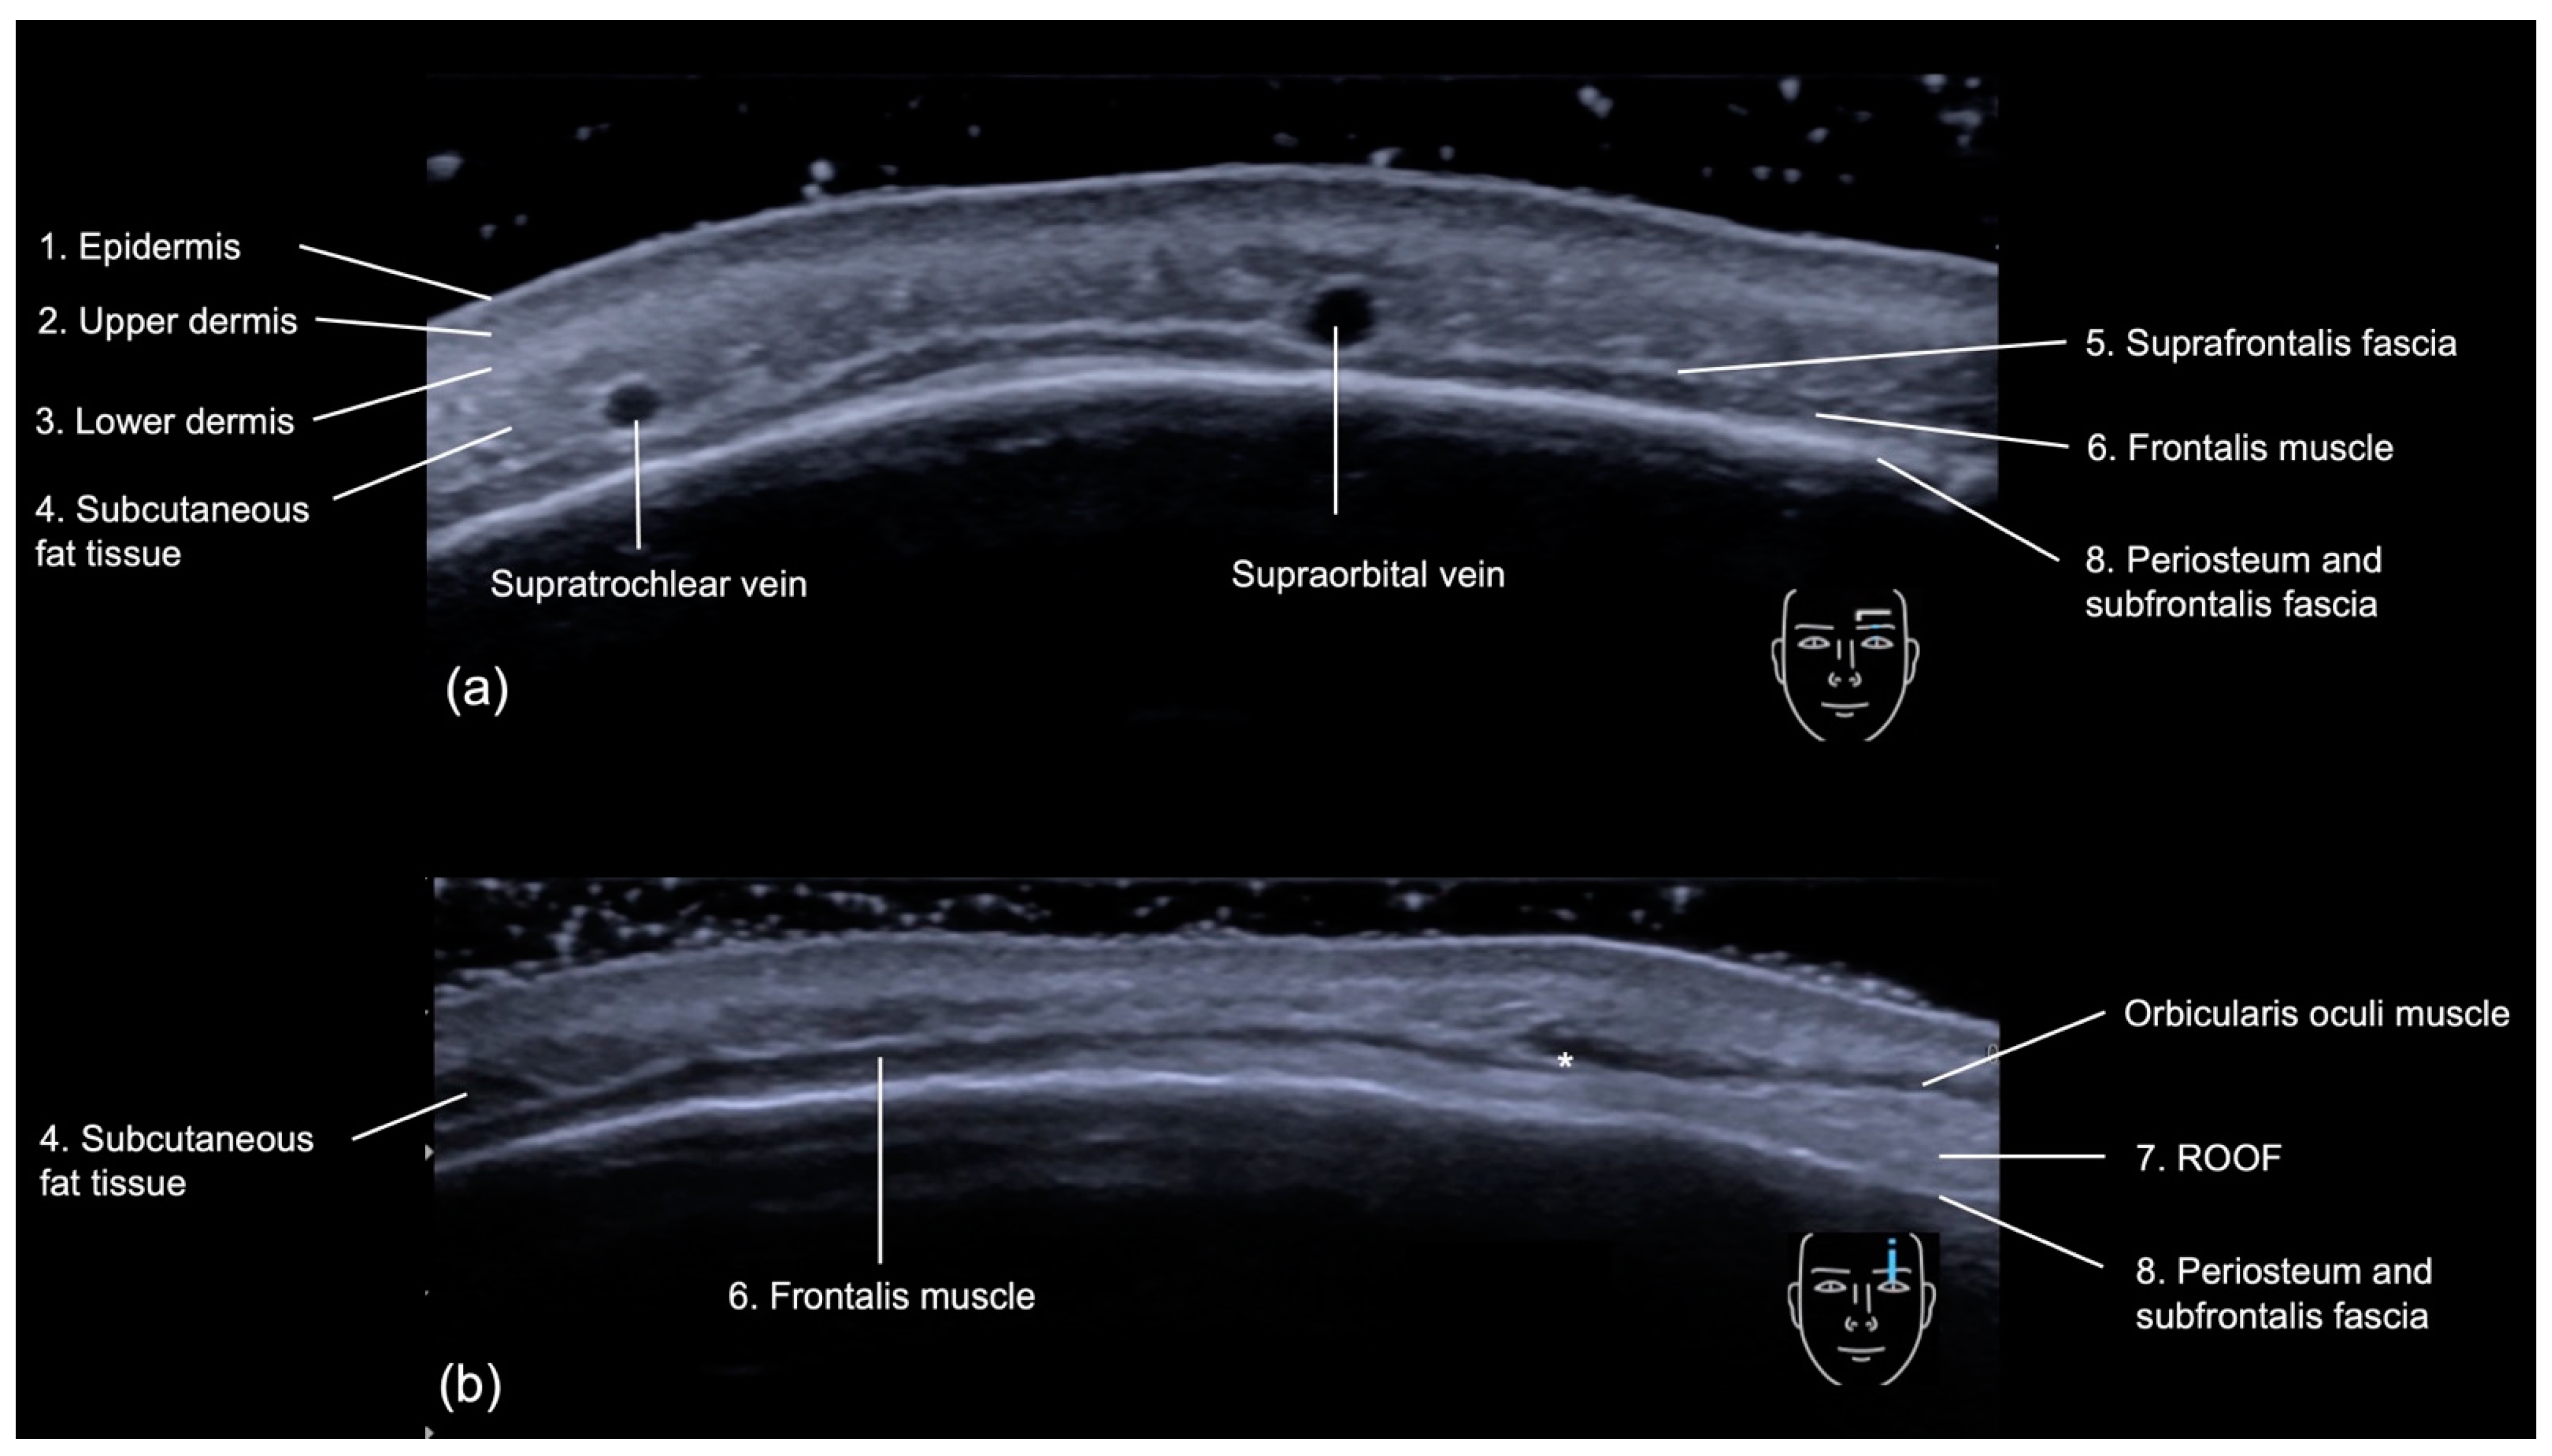

3.2.1. Sonographic Anatomy

- Epidermis: a hyperechoic line.

- Upper dermis: a hypoechoic homogeneous layer.

- Lower dermis: a hyperechoic layer.

- Subcutaneous fat tissue: a hypoechoic layer composed of fat lobules and hyperechoic septae.

- Suprafrontalis fascia: a thin hyperechoic upper layer of galea aponeurotica.

- Frontalis muscle: a hypoechoic band-like structure.

- Retro-Orbicularis Oculi Fat compartment (ROOF): a hyperechoic fibrous fat layer that separates the frontalis muscle from the bone. It can be appreciated in the inferolateral part of the forehead.

- Periosteum and subfrontalis fascia: a hyperechoic line showing combined imaging of these structures, with acoustic shadowing below. Due to the convexity and reflective nature of the frontal bone, there is usually a mirror imaging artefact.